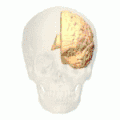

Position of cuneus(red) of left cerebral hemisphere.